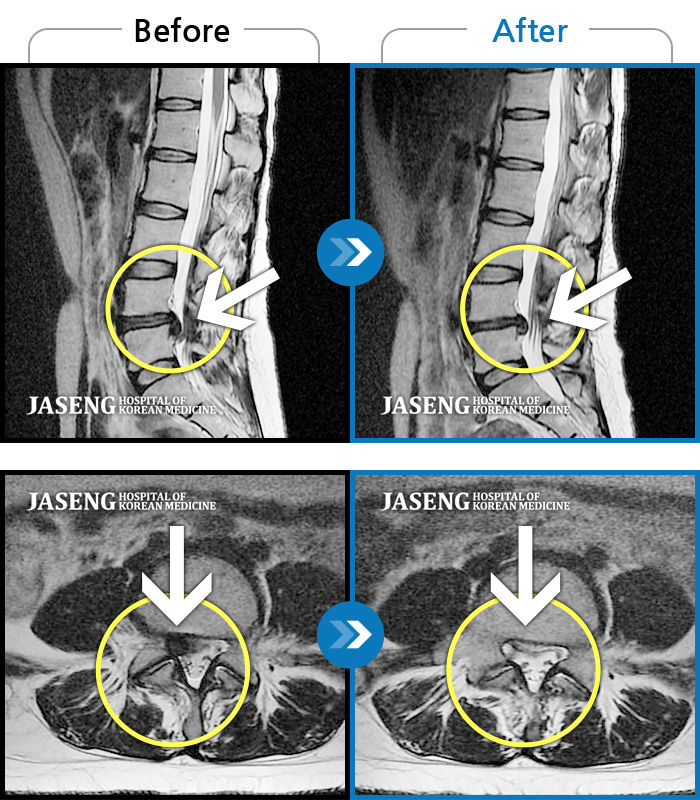

Before

After

환자에게 사전 동의를 받아 동일 조건에서 촬영되었습니다.

개인에 따라 치료 후 부작용이 발생할 수 있으니 의료진과 상담 후 치료를 진행하시기 바랍니다.

허리 통증과 좌측 다리 마비 증상

좌측다리로 저리고 통증, 허리 숙일 때 다리 당김